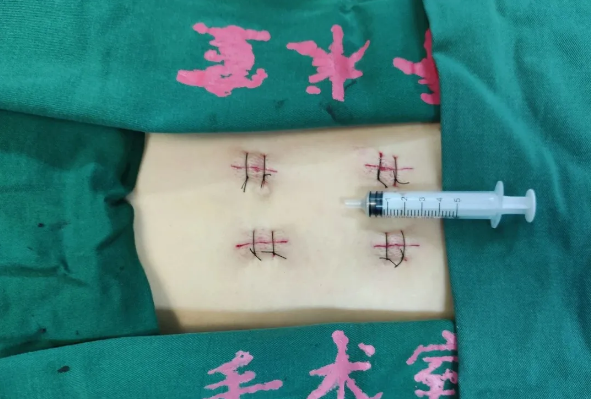

近日,天玑®骨科手术机器人落户南昌市第一医院,助力骨盆骨折闭合复位内固定术顺利完成。作为江西省首先采用5G引导下的骨科机器人手术,天玑®骨科手术机器人用它的“透视眼”,以三维影像扫描进行深层三维空间精准定位,为患者“量身定做”了最理想、最安全的教科书般通道,完成了复杂骨盆骨折微创治疗一次性完美置钉及腰椎骨折微创经皮置钉的首秀,成为江西省骨科发展的标志性事件,同时也是江西省骨科步入新型数字智慧骨科时代的重要里程碑事件。

患者为22岁年轻女性,因车祸致骨盆骨折。骨盆骨折是一种复杂的创伤,传统手术方式需要比较大的切口,而且骨盆内有大量复杂血管和神经,手术难度和风险极大,是很多骨科医生的禁区。

在南昌市第一医院廖琦教授带领下,由创伤骨科团队借助天玑®骨科手术机器人为患者“量身定做”最理想、最安全的教科书般的通道,完美安全微创完成手术,并且手术时间明显缩短,真正做到“指哪儿打哪儿”!更让患者放心的是,天玑®骨科手术机器人的“稳定手”机械臂进行精准定位,不用反复探寻。

由于天玑®骨科手术机器人的精准及高效,可以使手术时间明显缩短,因此在骨盆骨折手术后,在廖琦教授指导下,脊柱外科团队利用天玑®骨科手术机器人同样为20岁女性腰椎骨折患者“量身定做”最理想、最安全的教科书般的通道,完美安全微创完成手术,手术不仅时间缩短,并且出血和透视减少。